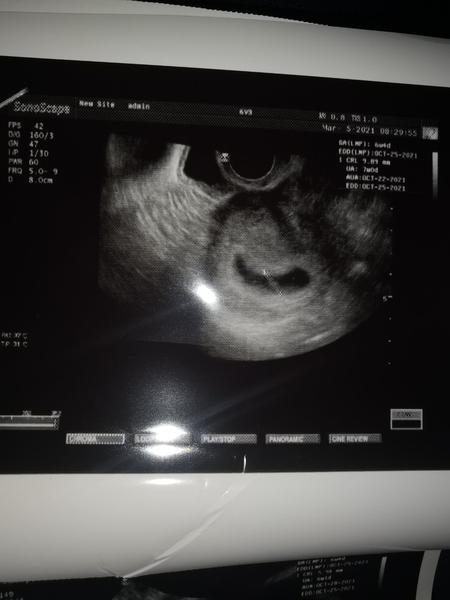

@valentina12345 áno ja. My sme boli 7 týždeň na sono. Jedno ma 1cm a ♥ bije a druhy ma 6mm a ešte bez ♥. Takže budúci týždeň idem opäť na sono